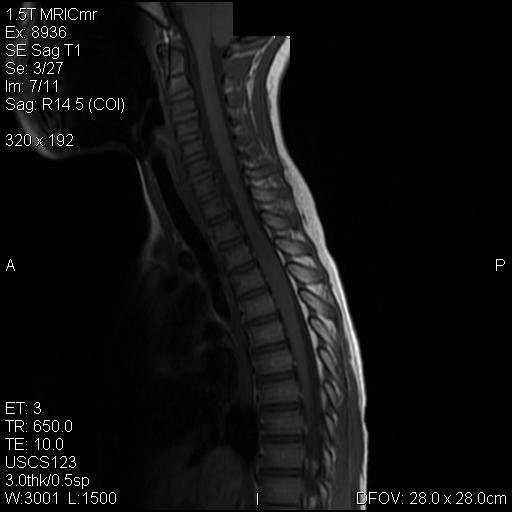

A. T1 |

Panel A to E are MR images. Panel F and G are taken from intraoperative cytologic preparation. Panel H to M are taken from frozen section. Panel N and O are from paraffin section. These sections are stained by hematoxylin-eosin stain. Panel P is immunohistochemistry for neurofilament proteins. Panel Q is stained by Luxol fast blue-Periodic acid Schiff (LFB-PAS) stain.

MR Imaging:

The segment of spinal cord at T3-T4 level is expanded and is accompanied by edema that runs from T2-T6. The expansion and edema is roughly symmetrical along the long axis of the cord. The expanded levels are isointense to the white matter of the spinal cord on T1-weighed images (Panel A). The edema is best demonstrated on T-weighed images (Panel B, C, and E). Patchy and poorly defined enhancement is demonstrated in the expanded areas (Panel D). The remaining levels of the spinal cord and the brain are free of abnormal changes.